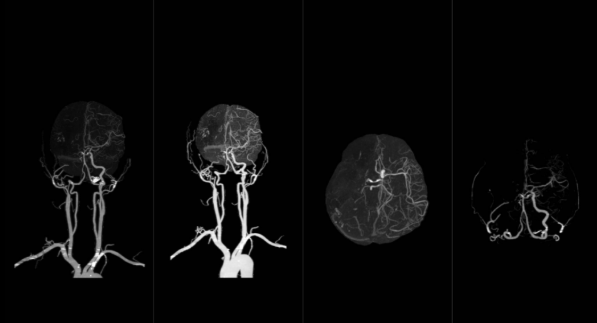

2、头颈联合血管CTA:

头颈部的主要血管有颈动脉、椎动脉、基底动脉、Willis环及大脑前、中、后动脉。CTA可清晰显示头颈部各血管的形态、位置及与临近组织的关系;可较好的判断颈动脉和椎动脉狭窄的部位、程度;清晰显示颈动脉体瘤与颈内、外动脉的关系;